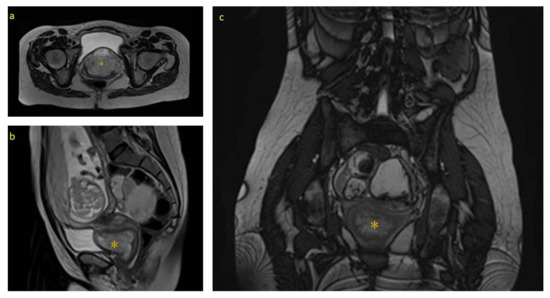

An Unusual Cause of Inguinal Mass in a Patient with Urolithiasis: A Case Report of Deep (Aggressive) Angiomyxoma in a Male Patient

by Christodoulos Chatzigrigoriadis, Vasileios Tatanis, Theodoros Spinos, Angelis Peteinaris, Angelos Samaras, Anastasios Thanos, Evangelos Liatsikos and Panagiotis Kallidonis

Clin. Pract. 2024, 14(6), 2705-2712; https://doi.org/10.3390/clinpract14060213 - 13 Dec 2024

Background: Deep or aggressive angiomyxoma is an uncommon neoplasm of the pelvis. Although deep angiomyxoma is a benign tumor, its tendency to infiltrate soft tissues and reach a large size (typically > 10 cm) indicates aggressive biological behavior. It is usually present in female patients, but there have been recent reports of male-aggressive angiomyxoma. While rare, it is an important consideration in patients with a pelvic mass. The clinical presentation is non-specific; patients are either asymptomatic or present with non-specific complaints, such as dull pain, constipation, and dysuria. It is commonly mistaken for an inguinal hernia, hydrocele, testicular cancer, lipoma, and epididymal cyst in male patients, thus misguiding the management of these cases. Hence, preoperative evaluation with imaging studies (ultrasound, computed tomography, magnetic resonance imaging) and biopsy allows for an accurate diagnosis and treatment. Currently, the standard of treatment is surgical resection of the tumor with free margins. The role of hormone therapy is under investigation for patients with deep angiomyxoma positive for estrogen/progesterone receptors. Regular follow-up is necessary given the high recurrence rate of deep angiomyxoma (9–72%). Methods: We present a case of an elderly man who presented with hematuria due to urolithiasis and an asymptomatic inguinal mass mimicking an inguinal hernia. A computed scan (CT) of the abdomen confirmed the presence of the mass, which was removed surgically. Results: The pathologic examination of the tumor was consistent with deep angiomyxoma. Conclusions: The diagnosis of deep angiomyxoma should always be considered in patients with an inguinal mass to avoid delayed treatment and incomplete surgical excision. Full article

Figure 1